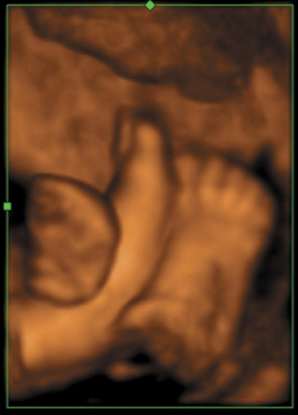

Voluson i image of foetal feet |

GE's Compact Series has now been expanded to include the new Voluson i

and LOGIQ i systems — each "i" product is designed to bring specialized,

console-quality imaging performance and portability to traditional

applications. Voluson i is designed for Obstetrics & Gynecology

applications, while the LOGIQ i will serve the general imaging needs of